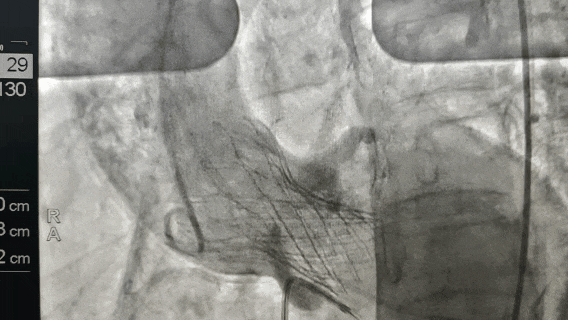

手术在介入导管室顺利开展,无需开胸、无需体外循环,医生通过股动脉穿刺建立微创通道,将压缩的人工瓣膜通过导管精准输送至主动脉瓣位置并缓慢释放。

术中,超声科实时监测瓣膜定位与功能,麻醉科提供平稳的生命体征支持,介入导管室护理团队默契配合,确保手术无缝衔接、精准高效。